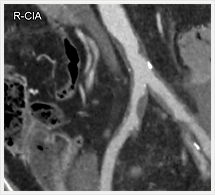

画像紹介(ステントグラフト編)

ステントグラフトは、人体に馴染みやすい人工布を筒状に形成し、これにステントといわれるバネ状の金属を縫い付けた人工血管で、これをストロー状のチューブで、患者さんの太ももの付け根から動脈内に挿入します。ステントグラフトを動脈瘤のある部位まで進め動脈瘤の内側ステントグラフトを挿入します。そうすることで動脈瘤の拡大を抑え、動脈瘤が拡大しなければ破裂する危険性がなくなります。このように、ステントグラフトによる治療は外科手術に比べて切開部が小さく、身体への負担が極めて少ない低侵襲血管内治療です。

ステントグラフト挿入術直後の造影

(上部)

(下部)